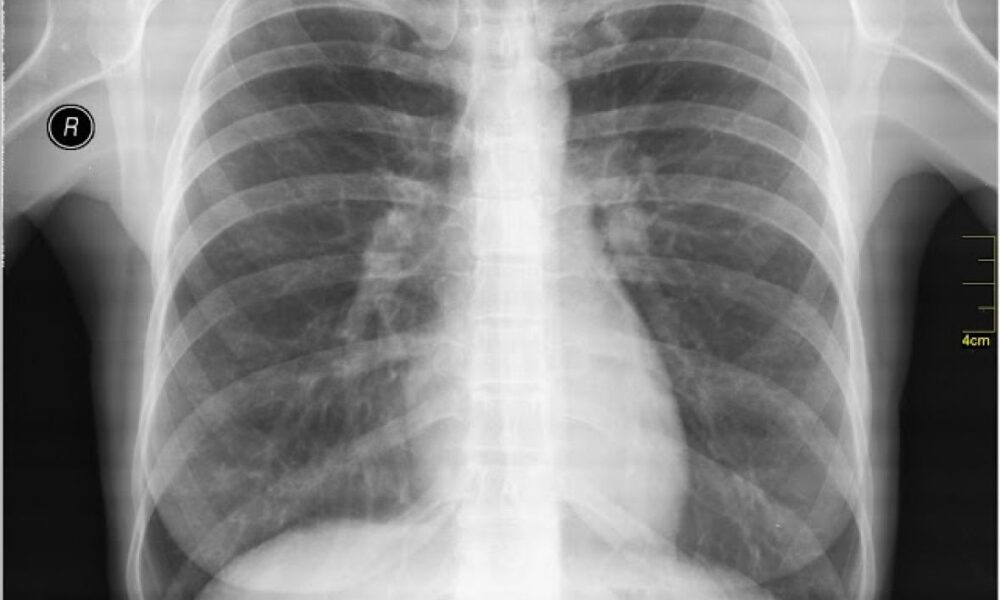

Obostrana upala pluća: Ozbiljna infekcija koja može biti fatalna

Simptomi, faktori rizika i kada se hitno javiti ljekaru